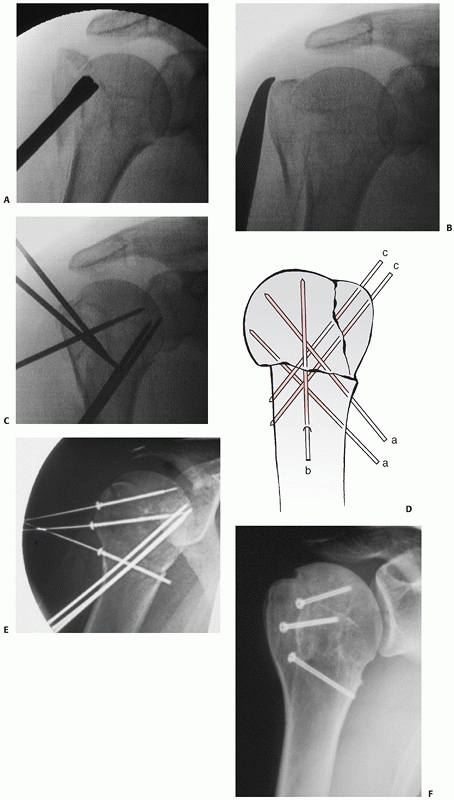

FIGURE 35-19

Posterior fracture dislocations are of three subtypes, as shown in these schematic illustrations: In Type 1 injuries, there is a fracture of the anatomic neck alone (A); in Type II, there is in addition a lesser tuberosity fracture (B); and in Type III, there is in addition a “shield” fracture consisting of the lesser tuberosity, the bicipital groove, the anterior portion of the greater tuberosity, and frequently an adjacent marginal portion of the articular surface (C). These injuries may be missed on the standard anteroposterior radiograph (D) in the emergency department but are always identifiable on modified axial views (E). |